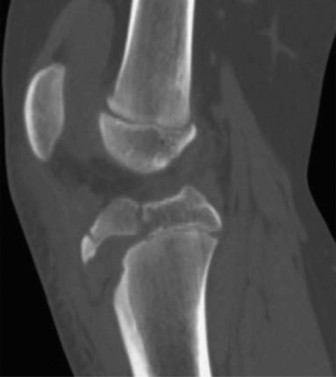

Risk of overgrowth in children who sustain diaphyseal femur fractures? CASE 9 A 14-year-old boy is brought to the ER with complaints of right knee pain after he was injured playing basketball. X-rays and a CT scan (CT Shown in Fig. 10–12) were done at an outside hospital and he was transferred to you for care.

Illustration 3 for Pediatric Cases: Optimal Closure of the Distal Femur

Clinical Radiograph / Orthopedic Image

Figure 10–12

What condition is thought to be a risk factor for this fracture?

The correct answer is (B). Tibial tubercle fractures occur more commonly in adolescents with a history of Osgood–Schlatter disease, but a causal relationship has yet to be demonstrated. Osgood–Schlatter disease is an overuse injury caused by repetitive strain across the tibial tubercle apophysis. Tibial tubercle avulsion fractures are not known to occur more commonly in young people who have patellofemoral syndrome (anterior knee pain associated with overuse), Sinding-Larsen–Johansson syndrome (a condition similar to Osgood–Schlatter, affects the lower pole of the patella, not the tibial tubercle and therefore not associated with tibial tubercle fractures), nor in people who have inflammation of the patella tendon. Therefore, choices A, C and D are not correct.